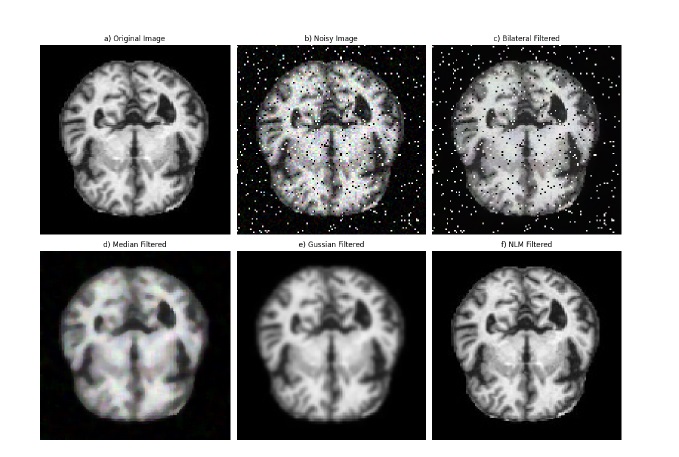

Noise reduction: Non-Local Means (NLM) filtering was employed for noise reduction in MRI images. NLM is a powerful denoising technique that works by averaging similar patches in the image, regard- less of their spatial proximity, to preserve fine details and structures while reducing noise. Unlike traditional filters, such as the Bilateral, Median, and Gaussian filters, which rely on local neighborhood information, NLM takes into account the global image content, making it particularly effective in preserving image textures and structures.

The key advantage of NLM over other filters lies in its ability to handle noise without introducing blurring or losing important details, which is crucial in medical imaging where fine structures, such as anatomical boundaries, need to be preserved. In this study, the NLM filter was applied with optimized parameters based on empirical evaluations.

Bilateral filter: The Bilateral filter smooths images while pre- serving edges by considering both spatial proximity and intensity similarity. However, it may struggle with complex textures or high levels of noise, often leading to blurring at edges.

Median filter: The Median filter is widely used for noise removal by replacing each pixel’s value with the median of the intensities within a defined neighborhood. It is particularly effective at preserving edges and removing outlier noise, but it may not perform well for large or dense noise patterns, potentially leading to the loss of fine details in the image.

Gaussian filter: The Gaussian filter is a linear smoothing technique that applies a Gaussian function to average pixel intensities over a region. It is effective in reducing random variations and smoothing the image but tends to blur edges and reduce the visibility of fine structures, which can impact the clarity of critical features in applications such as medical imaging. Theoretically, NLM outperforms these filters for medical images due to its ability to preserve intricate structural details while efficiently removing noise. This makes it particularly suited for applications like MRI, where maintaining the clarity of anatomical features is critical for accurate diagnosis and analysis. In the results section, we demonstrate the superiority of the NLM filter through visual comparisons and numerical evaluations against the other filtering techniques.

Comparison of Denoising Methods

MRI images are often affected by various types of noise introduced during the scanning process, including salt and pepper noise, speckle noise, and random noise, as illustrated in Figure 3. Effective noise removal is crucial to ensure accurate diagnosis while preserving essential anatomical structures. In this study, the denoising process addresses these three types of noise by applying four different filters to the corrupted images, aiming to remove noise without degrading the original image content, as shown in Figure 3. To evaluate the effectiveness of the proposed denoising methodology, the performance of each filter is assessed based on visual quality and quantitative metrics. The Peak Signal-to-Noise Ratio (PSNR) and Mean Squared Error (MSE) are computed to measure the effectiveness of noise reduction while maintaining image fidelity. The Mean Squared Error (MSE) is a widely used metric to measure the average squared difference between the original image Ioriginal(x, y) and the denoised image Idenoised(x, y). It is calculated as follows:

Figure 3. Visual comparison of denoising methods: (a) Original MRI image, (b) Noisy image, (c) Bilateral Filter, (d) Median Filter, (e) Gaussian Filter, (f) NLM Filter.

Table 2 presents a comparative analysis of image quality using these metrics for the applied filters: 2D Median Filter, 2D Bilateral Filter, 2D Gaussian Filter, and 2D Non-Local Means (NLM) Filter. The results demonstrate that the 2D NLM filter outperforms the other methods, achieving the highest PSNR of 55.29 dB and the lowest MSE of 0.19. This indicates its superior capability in reducing noise while preserving fine structural details. The Gaussian filter also shows reasonable performance, whereas the bilateral and median filters, while effective to some extent, introduce more residual noise and less detail preservation. These findings support the selection of the NLM filter as the optimal choice for MRI image denoising.